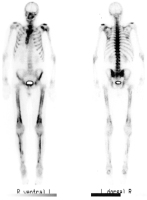

Abbildung 1: Ganzkörperszintigraphie nach Injektion von 500 MBq Tc99m-DPD aus dorsaler und lateraler Projektion. Periostal und kortikal entlang den Femora und Tibiae sowie im Bereich des Gesichtsschädels, der Scapulae und Claviculae zeigen sich pathologisch erhöhte Knochenstoffwechselaktivitäten.